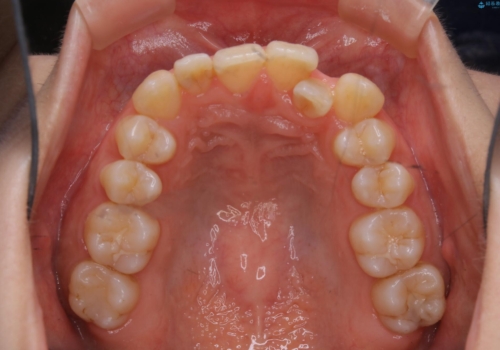

- 上の前歯が1本後ろに入ってしまっていることが気になるとご相談にいらした方です。

元々下の前歯が1本欠損しており、上下の噛み合わせや、歯のサイズバランスを考慮しながら治療を行いました。

下顎切歯が1本欠損しているため、上顎前歯部を少しずつストリッピングして、上下の噛み合わせ、バランスの向上を図りました。